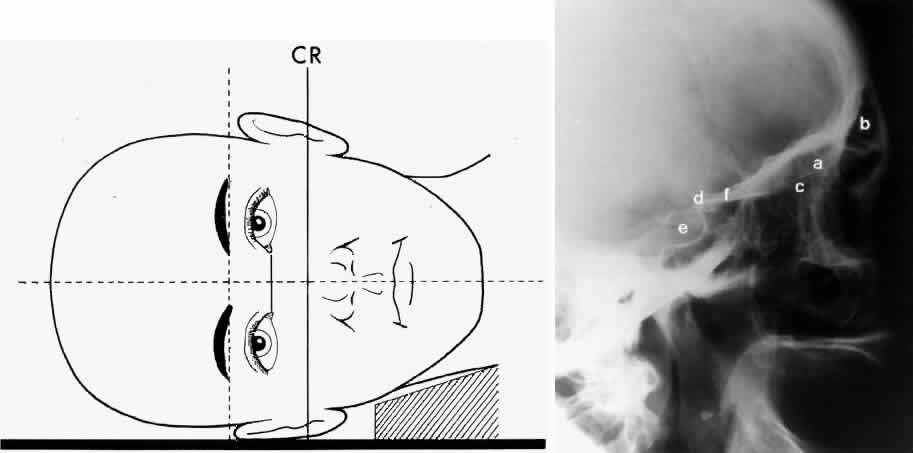

Lateral projection (Fig. 4) is created by placing the patient's head against the x-ray cassette and centering the cassette on the lateral canthus. The x-ray beam is directed perpendicularly to the midpoint of the cassette and enters the patient's head at the lateral canthus remote from the cassette.5,6 This projection provides a view of the sagittal plane of the skull. Because of the overlapping skeletal structures, interpretation of unilateral disease processes is difficult. The structures that can be identified and best evaluated include the sphenoid, frontal, ethmoid, and maxillary sinuses. This lateral view also shows the sella turcica, the anterior and posterior clinoid processes, the nasopharynx, and the cribriform plate. The orbital structure best evaluated is the orbital roof. The floor of the orbit is visible but evaluation is difficult because of the upward slope, from lateral to medial, toward the orbital apex. This slope causes the floor to appear at different levels on the lateral view.11 The lateral projection, although not as useful as the frontal projections, gives information concerning air-fluid levels in traumatized patients, when only a horizontal projection is possible.

Fig. 4. A. Schematic showing positioning for a lateral projection. (CR, central ray) B. Radiograph of a lateral projection. (a, orbital roof; b, frontal sinus; c, ethmoid sinus; d, anterior clinoid process; e, sella turcica; f, planum sphenoidale) (A; Rao VM, Gonzalez CF: Plain film radiography and polytomography of the orbit. In Gonzalez CF, Becker MH, Flanagan JC [eds]: Diagnostic Imaging in Ophthalmology, pp 1–7. New York, Springer Verlag, 1986)